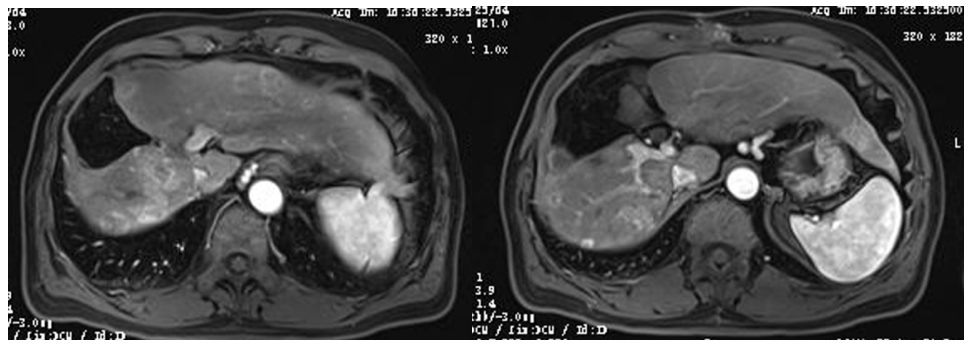

2020年10月22日(3次TACE 瑞戈非尼 卡瑞利珠单抗4个疗程),复查腹部和胸部CT示,肝脏部位碘油沉积良好,病灶趋于缩小状态,肺部病灶基本消失(图5)。AFP由53ng/ml降至4.5ng/ml。疗效评价为部分缓解(PR)。

图5.2020年10月22日胸部和腹部CT

2021年3月3日(根治术后4个月,瑞戈非尼 卡瑞利珠单抗持续治疗)复查CT示,肺部病灶消失,未发现新生病灶;复查MR示,肝脏残留病灶切除后未见明确新发病灶(图6)。AFP正常,疗效评价达到完全缓解(CR)。

图6.2021年3月3日复查CT及MR

2021年11月4日(根治术后1年,瑞戈非尼 卡瑞利珠单抗持续治疗)复查CT及MR示,肺部无明显病灶,肝脏无明确新发病灶(图7)。AFP正常。至今,持续缓解超20个月。

图7.2021年11月4日复查CT及MR